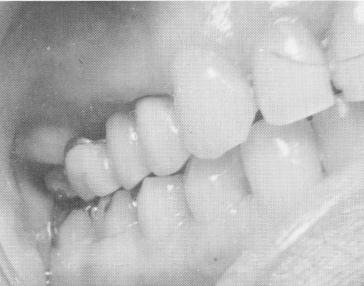

Fig. 15-66. The occlusion was once again checked. Sutures were used to close the wound.

2 Occlusion checked after upper endosseous pin implantation